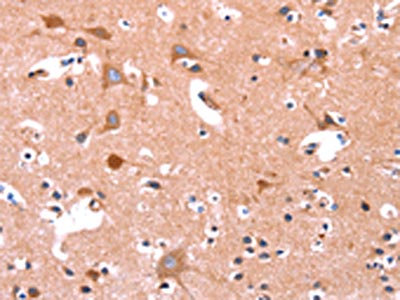

The image on the left is immunohistochemistry of paraffin-embedded Human gastic cancer tissue using CSB-PA196653(ABI1 Antibody) at dilution 1/40, on the right is treated with synthetic peptide. (Original magnification: ×200)

The image on the left is immunohistochemistry of paraffin-embedded Human brain tissue using CSB-PA196653(ABI1 Antibody) at dilution 1/40, on the right is treated with synthetic peptide. (Original magnification: ×200)